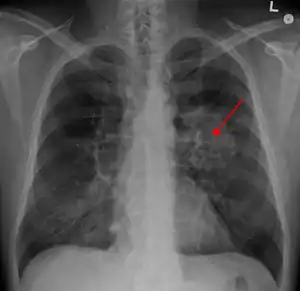

| A chest X-ray showing a tumor in the lung (marked by arrow) | |

Performing a chest radiograph (x-ray) is one of the first investigative steps if a person reports symptoms that may be suggestive of lung cancer. The x-ray may reveal an obvious mass, the widening of the mediastinum (suggestive of spread to lymph nodes there), atelectasis (lung collapse), consolidation (pneumonia), or pleural effusion.[14] Computed tomography (CT) imaging of the chest is often used for diagnosis and may reveal a spiculated mass which is highly suggestive of lung cancer. CT imaging is also used to provide more information about the type and extent of disease. Bronchoscopic or CT-guided biopsy is often used to sample the tumor for histopathology.[15]

Lung cancer can often appear as a solitary pulmonary nodule on a chest radiograph. However, the differential diagnosis is wide and many other diseases can also give this appearance, including metastatic cancer, hamartomas, and infectious granulomas caused by tuberculosis, histoplasmosis, or coccidioidomycosis.[66] Lung cancer can also be an incidental finding, as a solitary pulmonary nodule on a chest radiograph or CT scan done for an unrelated reason.[67] The definitive diagnosis of lung cancer is based on the histological examination of the suspicious tissue in the context of the clinical and radiological features.[1][3]